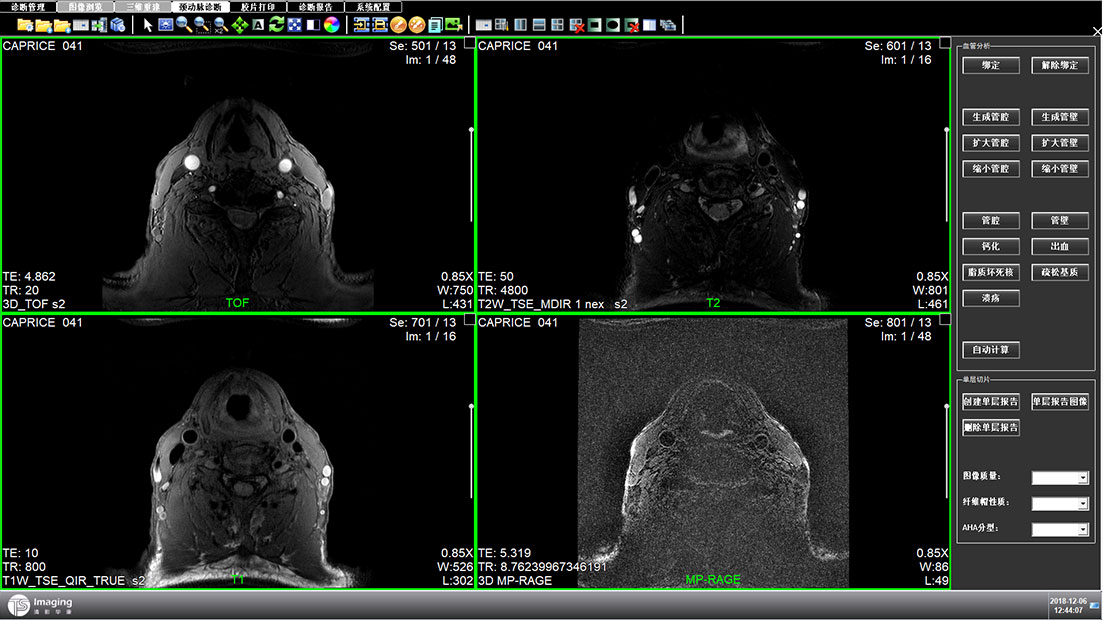

頸動(dòng)脈診斷頁(yè)面

頸動(dòng)脈診斷頁(yè)面整體布局和三維重建比較相似,最大的區(qū)別是右側(cè)的操作區(qū)域,血管分析都為按鍵操作,通過(guò)間隔的大小分成三部分。單層切片除了按鍵還有下拉菜單的操作。

頸動(dòng)脈診斷原型